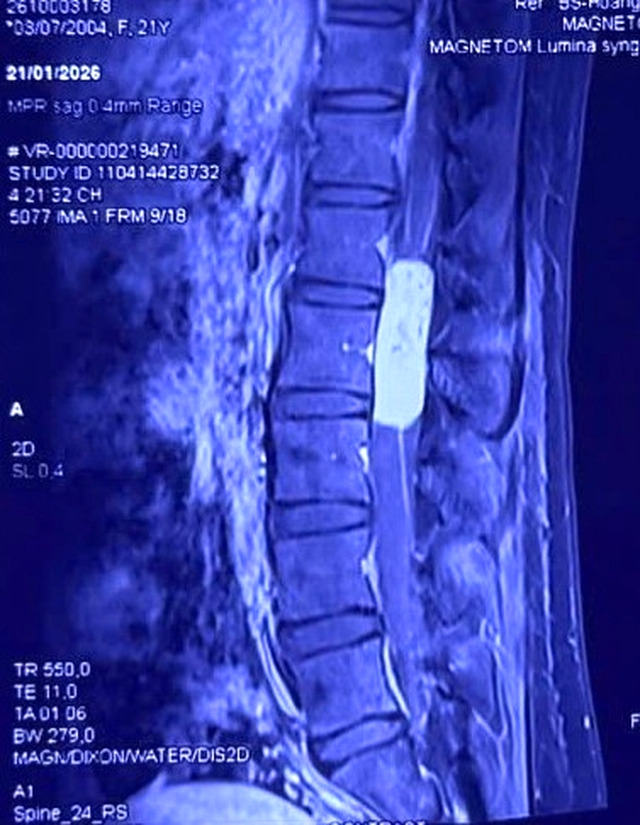

Hình ảnh khối u trên phim chụp cộng hưởng từ (MRI).

Kết quả chụp cộng hưởng từ (MRI) cho thấy chị H.L. có một khối u màng não tủy dài gần 10cm, kéo dài từ đốt sống L1 đến L3. Khối u "ôm trọn" tủy sống và các rễ thần kinh đuôi ngựa – vùng kiểm soát vận động, cảm giác của toàn bộ hai chi dưới.